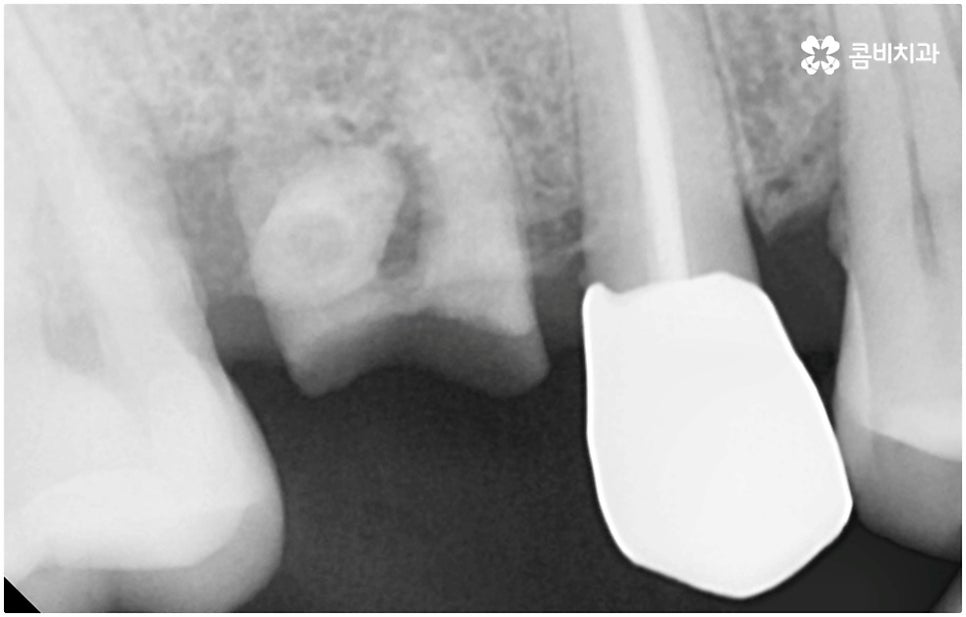

치아가 빠진 순간부터 이를 받치고 있던 치조골이 서서히 흡수되기 시작하므로 영구치가 빠지고 나서 시간이 많이 지나게 되면 부족한 잇몸뼈 부분을 뼈이식으로 보충해 주는 과정이 추가적으로 들어가야 하지만 이미 뼈가 손상된 경우가 아니라면, 즉시 식립을 하면 그럴 필요가 없는 거예요. 또한 잇몸이 이미 내려앉은 후 수복을 하려면 잇몸 라인이 인위적으로 만들어질 가능성이 높아지는데 치조골 소실이 크게 일어나기 전에 임플란트를 심게 되면 주변 치아 및 잇몸과 보다 조화롭게 맞출 수 있어서 심미적인 부담도 덜 수 있어요.

하지만 여기서 주의하셔야 할 점은 누구나 발치후 임플란트 를 즉시 식립할 수 있는 것이 아니라 바탕이 되는 잇몸뼈의 양이 충분하고 기존에 염증과 같은 잇몸 질환이 없는 분들의 경우에만 이용할 수 있는 방법이기 때문에 3D CT 등 정밀 분석 기계로 환자분들의 상태를 정확하게 진단한 후에 결정해야 한다는 거예요.

즉, 해당 분야의 임상 경험이 풍부한 숙련된 의료진분들이 계신 치과에서 자신이 발치후 임플란트 즉시 식립 방식이 가능한지 부터 확인하실 필요가 있는데요. 만약 다양한 이유로 인해 발치 후 즉시 심는 것이 불가능한 케이스라고 한다면 상황에 맞게 뼈이식, 상악동 거상술, 잇몸 질환 치료 등 선처치들을 먼저 해 주고 나서 충분한 회복 기간을 두고 임플란트 시술을 진행해야 식립 성공률 및 지속 가능성을 높일 수 있습니다. 이렇게 환자분들 각각의 상황을 고려하지 않은 채 발치 후 즉시 식립을 무리하게 진행하게 되면 임플란트의 위치를 제대로 고정하는 데 어려움이 있어 해당 치아로 잘 씹을 수 없게 되고 얼마 지나지 않아 다시 쓰러지거나 주변 치아와 잇몸에 압박을 가해서 지속적으로 좋지 않은 영향을 주게 되는 등 문제가 커질 수 있으니 주의하실 필요가 있어요.